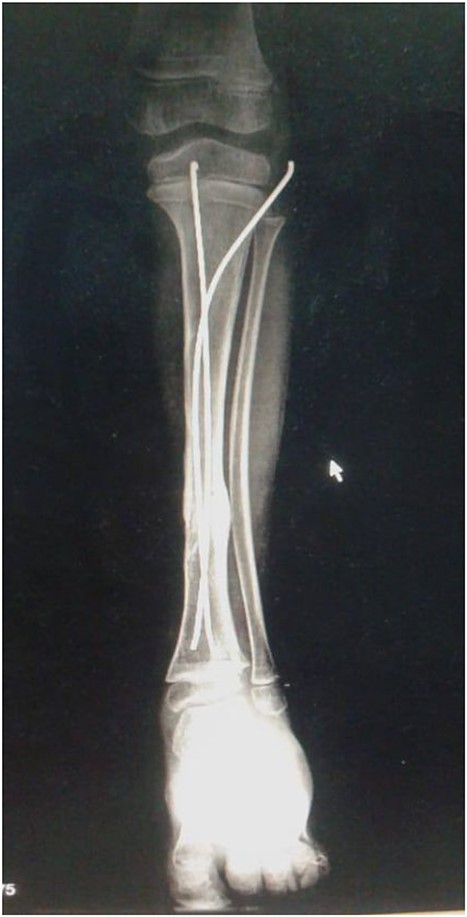

The decision to perform limb salvage surgery was made despite parental refusal and the consideration of the patient’s age. Initial debridement was performed in the supine position, with dislocations and fractures reduced and fixed using K-wires (Fig. 2). A temporary skewer was placed between the foot and the leg components to ensure stability. The patellar tendon, posterior muscles, and skin flap were meticulously sutured (Fig. 3). Postoperative follow-up showed satisfactory capillary refill, moderate sensation, and return of the anterior tibial artery pulse within three days. Progressive wound healing was observed over a month, allowing partial weight-bearing ambulation at 2 months (Fig. 4). Complete leg bone healing was achieved at 6 months, with removal of the flexible nail and restoration of the full range of motion and sensation (Fig. 5).

Shows the leg following the placement of the K-wire and prior to suturing the skin flap.